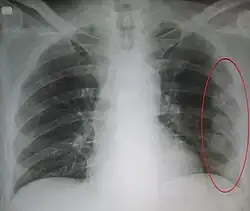

An X ray showing multiple old fractured ribs of the person's left side as marked by the oval